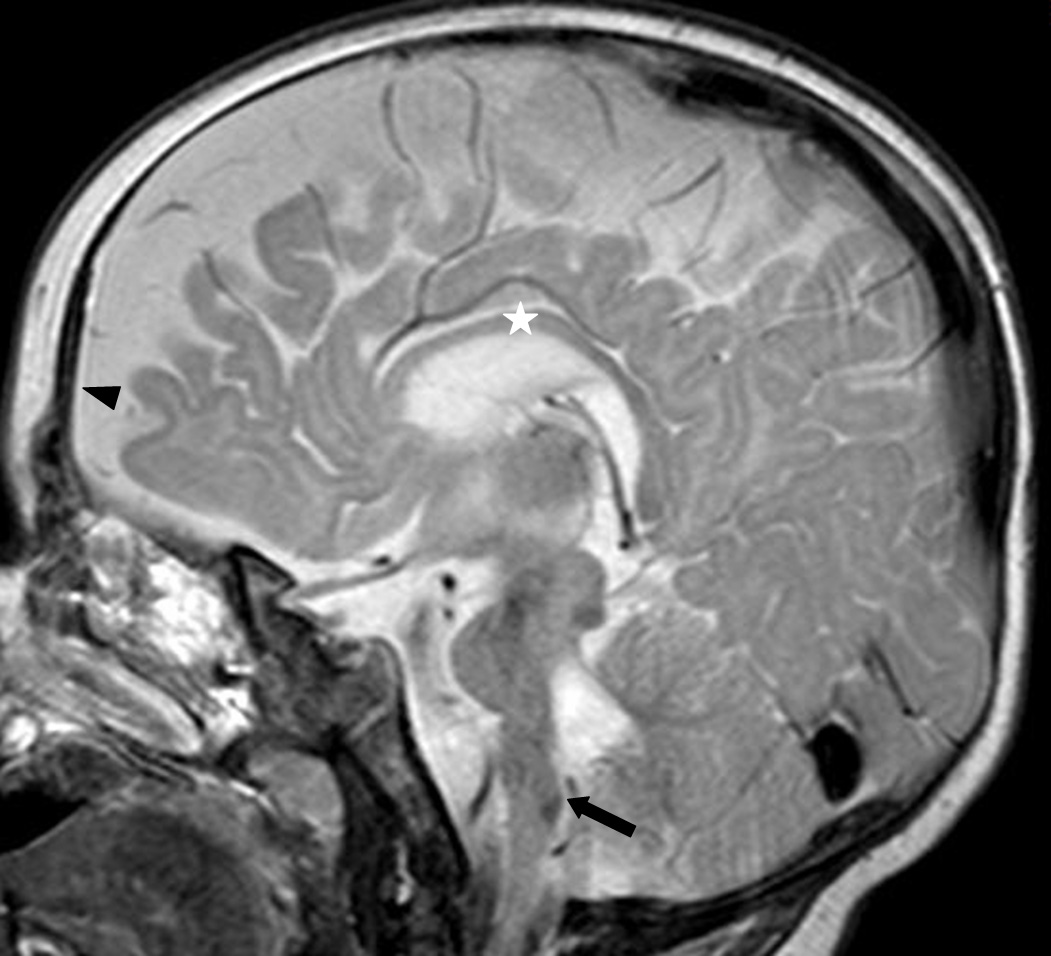

Figure 9 of Volk, Mol Vis 2011; 17:1978-1986.

Figure 9. Sagittal magnetic resonance imaging scan of patient 4 at the age of 6 months. The frontal lobes are hypoplastic (arrowhead). The corpus callosum is thinned (star) and the brainstem is flattened (arrow).